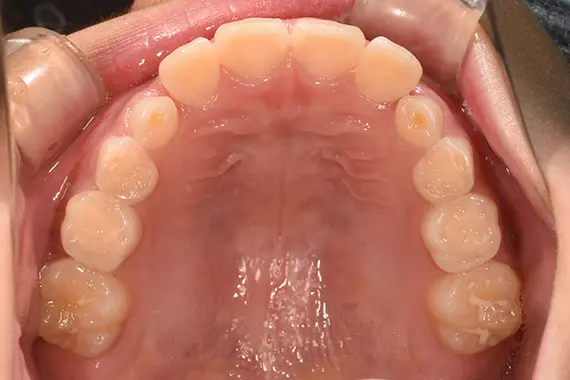

矯正後:上側

| 治療名 | ムーシールド使用の一期治療(就学前の一期治療) |

| 治療回数・期間 | 約3年(ムーシールド2年・一期治療1年) |

「受け口」への対処を早期の内に行うと、「上あごの成長阻害」という重大な弊害を回避することが出来ます。 「受け口」の治療は長期間になりますし、経過観察もしっかりと診てゆく必要がある治療です。 |